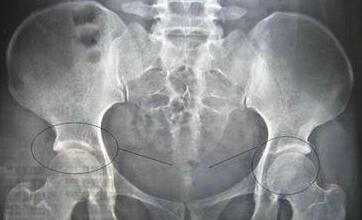

杜爱华主任在详细了解宋先生的情况之后,让他做了一个详细的检查,以确保治疗的正确性。检查结果显示:血沉89mm/h;C-反映蛋白34.25mg/L;HLA-B27(+);骶髂关节X片示:双侧骶髂关节面模糊、毛糙、不规则,关节附近骨质疏松,见斑点状及小囊状骨质破坏区及少许骨质增生硬化影,关节间隙模糊狭窄。根据这些检查结果,可以确诊为强直性脊柱炎。杜爱华主任根据检查数据为他制定了详细的治疗计划。

(图:患者来院时骶髂关节X线)